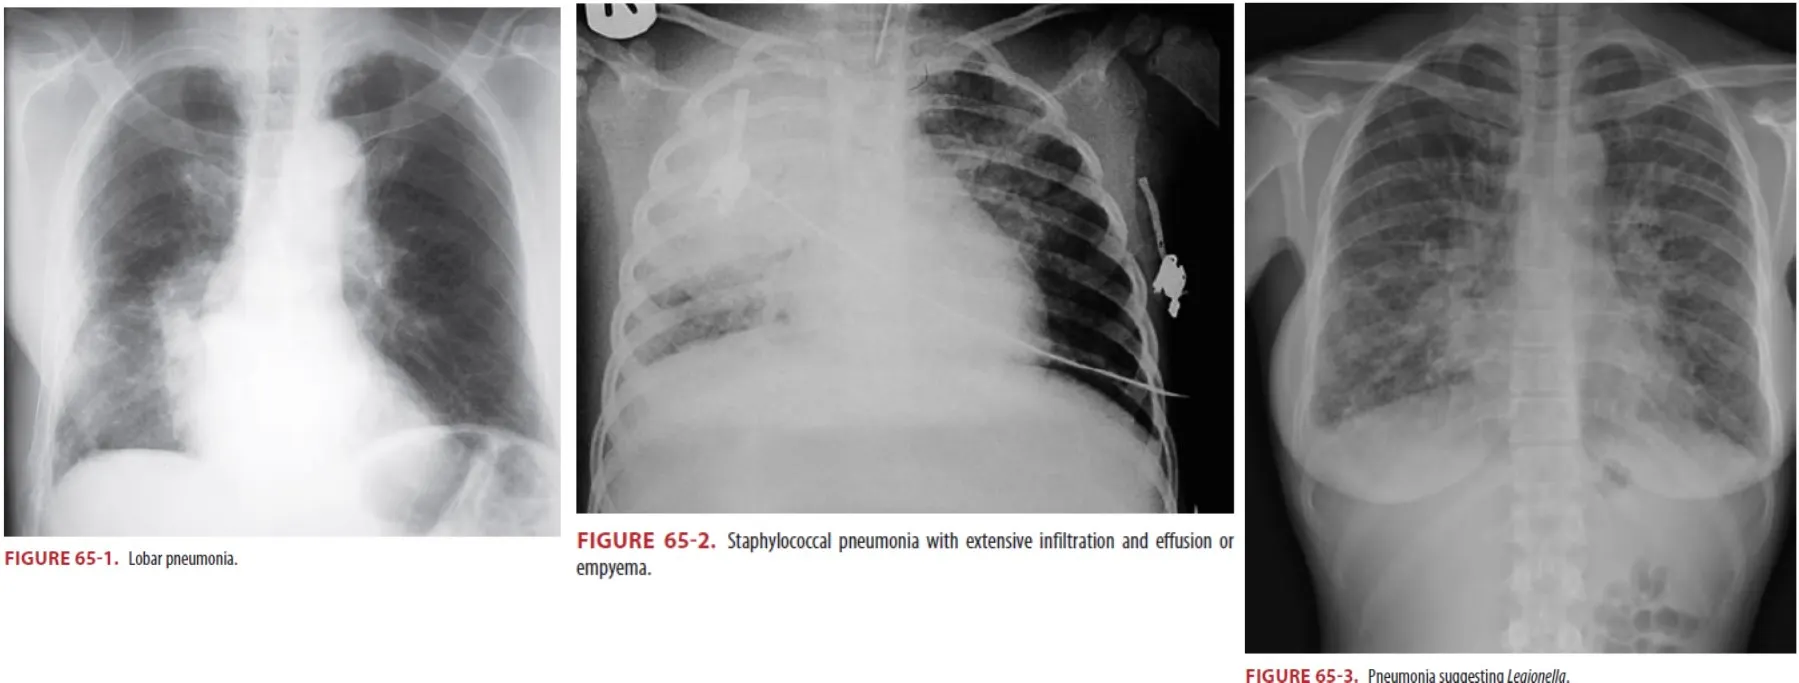

(1) S. aureus

① Insidious onset

② Extensive and multiple infiltrates with empyema, pleural effusions

③ Healthcare-acquired pneumonia are at risk for infection with MRSA

(1) Legionella

① No seasonality

② from benign self-limited disease to multisystem organ failure commonly complicated by

GI symptoms (abdominal pain, vomiting, and diarrhea)